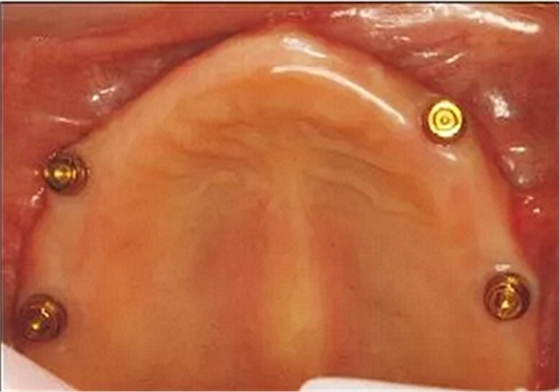

MLTR-Ⅱ類患者可以采用種植覆蓋義齒修復(fù)。牙槽嵴高度會(huì)影響到頜間間距,頜間間距會(huì)影響種植體相連的附著體的選擇。如果切緣到牙槽嵴頂間距離在12 mm以上可以采用桿卡固位方式;距離為10~12 mm可選擇球帽或者套筒冠修復(fù);距離為8~10 mm,可以選用Locator或者磁性附著體修復(fù)(圖5);如果距離低于8 mm,常需要去骨以獲得足夠的修復(fù)間隙[21],否則會(huì)造成修復(fù)困難。

本病例最小唇側(cè)基托邊緣位于前牙區(qū)牙槽嵴的冠方,前牙區(qū)牙槽嵴寬度可以支撐口唇凸度,但齦緣位置距離牙槽嵴頂距離大于4 mm,不是單純的牙缺失,為MLTR-Ⅰ類2亞類;與患者討論后決定采用復(fù)合式義齒修復(fù)。 采用微創(chuàng)技術(shù)進(jìn)行上下頜種植手術(shù)(圖10A),放置多基基臺(tái),制作臨時(shí)修復(fù)體(圖10B、D),待3個(gè)月種植體骨結(jié)合完成后,完成最終修復(fù)(圖10C、E和圖11)。